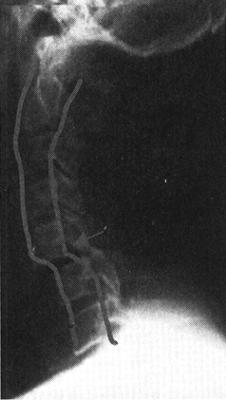

脊髓造影是一种有创伤性的检查,利用穿刺针向蛛网膜下腔内注入阳性造影剂使蛛网膜下腔和脊髓显影,从而了解脊髓受压情况和蛛网膜下腔的通畅情况。脊髓造影所用的造影剂为硬膜囊内注射专用碘造影剂,常用等渗非离子水溶性碘造影剂,其毒副作用小,很少产生过敏反应并且显影效果好。因而,脊髓造影仍然可作为了解脊髓病变的一种有效、安全的影像学检查方法,尤其对目前没有MRI设备的医院,脊髓造影仍然是了解椎管内病变的一种有效的检查方法(图7-3)。

图7-3 T12椎体压缩性骨折呈楔状改变,并向后突。脊髓造影显示,该水平蛛网膜下腔受压闭塞,呈双峰状

CT与MR出现以来,脊髓造影已不再常规使用。但在复杂的脊柱损伤CT扫描中,无法显示硬膜囊内结构,使用水溶性非离子型鞘内造影剂进行脊髓造影后CT扫描(CTM)扩展了CT在脊髓损伤中的应用(图7-11)。

图7-11 脊髓造影后多排螺旋CT扫描矢状面重建,可区分脊髓、神经根。蛛网膜下腔充满造影剂呈高密度,而脊髓、神经根呈中等密度